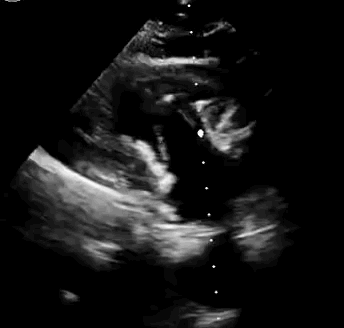

上海中山醫(yī)院葛均波院士、錢菊英院長(zhǎng)、周達(dá)新教授、潘文志教授、潘翠珍教授、李偉教授共同完成此次臨床前研究。術(shù)后葛均波院士對(duì)Lux-Valve Plus的器械操作性能給予了高度評(píng)價(jià),DSA和超聲影像也顯示出在本次研究中Lux-Valve Plus的安全性和有效性俱佳。

本次臨床前研究經(jīng)右側(cè)頸靜脈置入LuX-Valve Plus輸送系統(tǒng)可調(diào)彎鞘管,在DSA及超聲引導(dǎo)下將人工三尖瓣瓣膜植入到原有三尖瓣位置,利用獨(dú)特的錨定技術(shù)將人工瓣膜支架可靠固定在預(yù)定的位置。